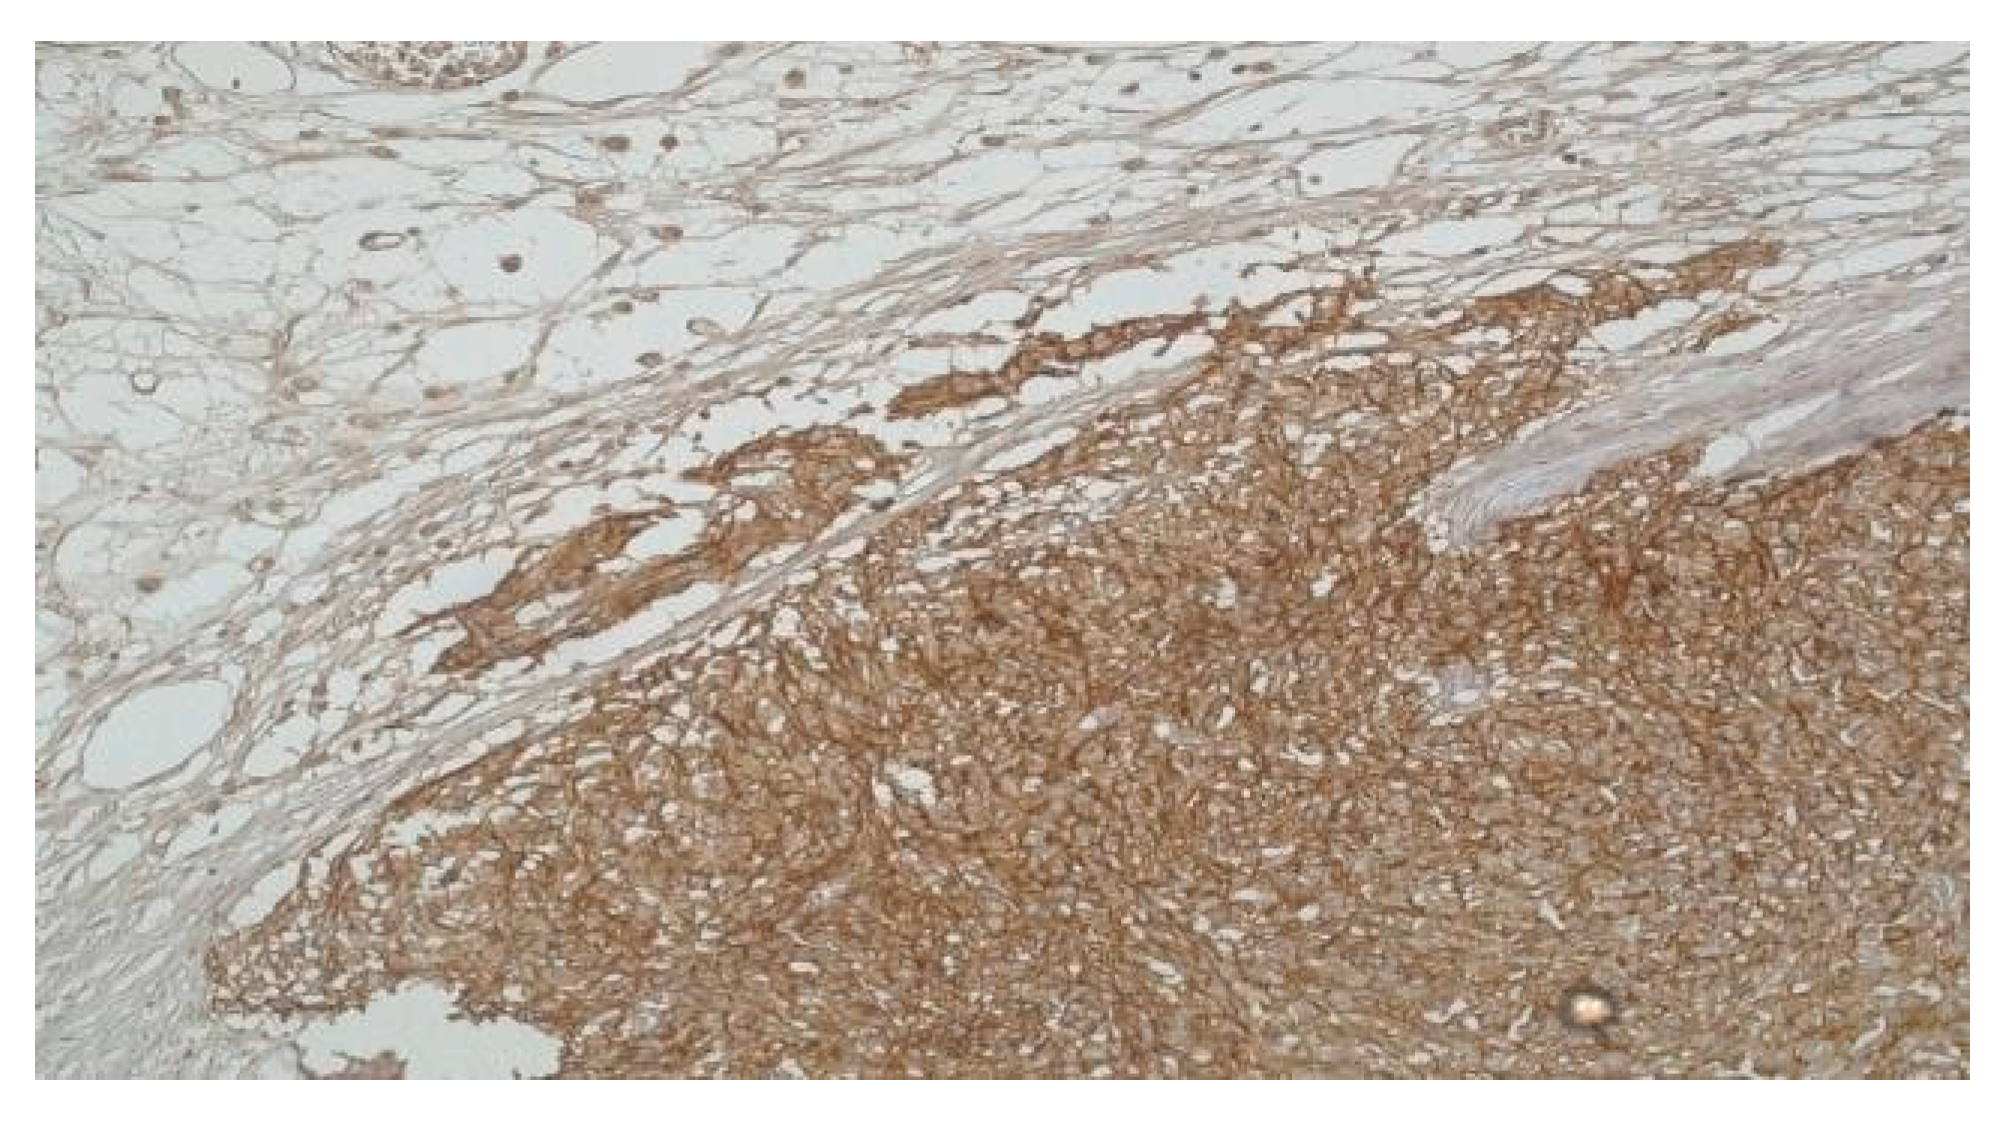

In tandem with CD117, the expression of CD34 also appears to exert influence on the risk profile GISTs. Notably, the majority of high-risk GIST cases (75%, encompassing 3 cases) exhibited significantly elevated levels of both ICCs and CD34 and only one high-risk GIST case presented with lower levels of ICCs and reduced CD34 expression.

Contrastingly, only 40% of cases classified as very low- risk (2 cases) and one case as low-risk displayed heightened levels of both ICCs and CD34. The remaining cases within the very low-risk and low-risk GIST categories consistently demonstrated diminished levels of both ICCs and CD34 (Figure 3). This pattern, mirroring that seen with CD117, further emphasizes the nuanced relationship between CD34 and the risk stratification of GISTs.

Figure 3. High-risk gastric GIST - Mixt pattern, fusiform and epitheliod (CD34 x 20) and High-risk gastric GIST - Mixt pattern, fusiform and epitheliod (H and E x 20).